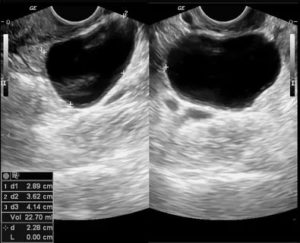

- УЗИ органов малого таза;